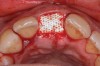

The right central incisor was removed atraumatically (Figure 3) without elevating a buccal flap. The presence of the buccal bone dehiscence was confirmed with the use of a periodontal probe. Measurements from the free gingival margin to the crest of the buccal bone and a horizontal assessment of the defect size indicated a dehiscence that was 8-mm tall and 5-mm wide. The distance from the free gingival margin to the most apical point in the socket was 10 mm.

Fig 3. Atraumatic extraction of central incisor.

Figure 3